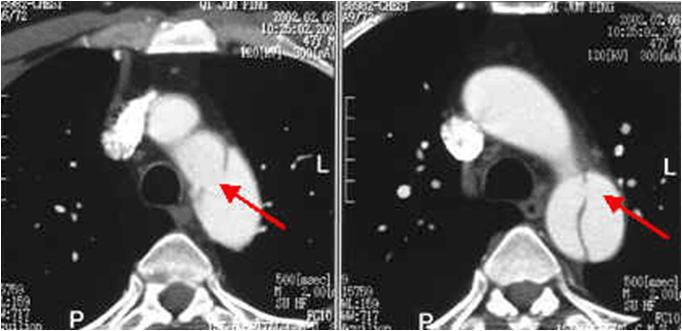

肺栓塞患者的CTPA表现:

肺栓塞患者的CTPA表现:右肺动脉开口处巨大血栓: